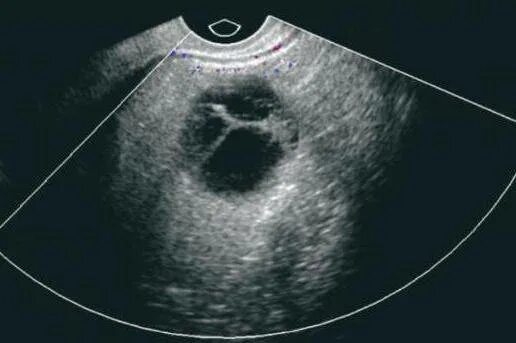

Почему болит яичник при овуляции